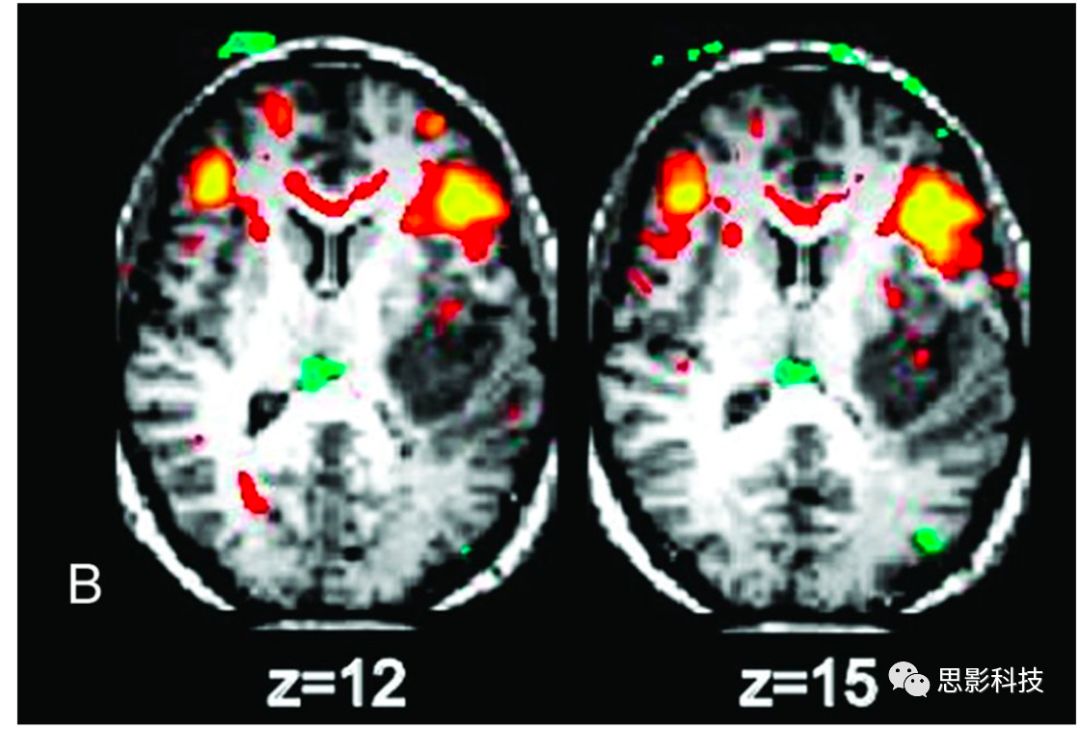

事件相關設計是另一類重要的功能磁共振成像實驗,其中HRF在其中起著核心作用。HRF原則上可以從適當?shù)氖录嚓P研究中獲得。Li等人的研究是識別與Stroop單詞-顏色干擾任務的事件相關的腦活動區(qū)域。Stroop相關激活腦區(qū)包括7個主要區(qū)域——前扣帶回、島葉、額下和額中區(qū)域和頂葉腦區(qū)。如圖10所示。從DTI中追蹤到與7個激活的GM區(qū)域相關的WM區(qū)域,如圖10所示,并且然后分析了這些WM區(qū)在每一個事件相關trail下的BOLD波形。雖然有幾個區(qū)域顯示出連續(xù)增加到一個單峰,類似于GM反應,但其他區(qū)域顯示出明顯的雙相波形,具有明顯的負下降,隨后出現(xiàn)正峰值。

Fig 10. 左上角:用標準GLM檢測Stroop試驗事件相關激活的皮層區(qū)域。上中圖:使用DTIROIs激活圖中追蹤與之相關的纖維束。右上角:20名受試者的7個灰質區(qū)域的矩陣,兩兩腦區(qū)之間所識別出來的WM纖維束(顏色)。下圖:20個受試者中的4WM區(qū)域中多個時間段的BOLD信號平均時間。紅線表示適合雙變量函數(shù),對照WM區(qū)域無明顯變化,反應平緩。